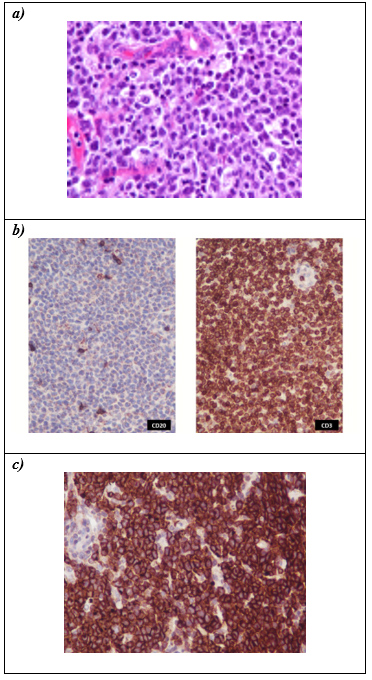

El estudio histopatológico, desde el punto de vista morfológico, mostró tejido ganglionar linfático difusamente infiltrado por células atípicas de gran diámetro, con moderado citoplasma eosinófilo pálido y núcleos marcadamente pleomórficos con nucléolo central prominente, destacándose frecuentes células de tipo "hallmark" con pronunciadas escotaduras nucleares (núcleos en “herradura”) (Figura 5.a). Ante este cuadro morfológico, en contexto de múltiples linfoadenopatías, el primer diagnóstico presuntivo a considerar fue una neoplasia de origen linfoide, independientemente del resultado de citometría de flujo.

Posteriormente se realizó la caracterización inmunofenotípica mediante técnica de inmunohistoquímica, realizando un primer panel de anticuerpos, con el que se llegó al diagnóstico preliminar descriptivo de linfoma de células T de alto grado histológico, observándose positividad para CD3 (marcador de diferenciación linfoide T), negatividad para CD20 (marcador de diferenciación linfoide B) (Figura 5.b) y un alto índice de proliferación (Ki67~95%). El panel complementario mostró positividad fuerte y difusa para CD30 y coexpresión para CD43, CD4 y CD2, y negatividad para CD5, CD8, CD56, Granzima B y Pax5.

El contexto clínico e histomorfológico, con presencia de frecuentes células de tipo “hallmark”, asociado a un fenotipo T (CD3+CD4+CD2+) con destacada expresión de CD30 (Figura 5.c), configuran los criterios diagnósticos del linfoma anaplásico de células grandes, haciéndose el diagnóstico diferencial con otras entidades linfoides de linaje que puede expresar CD30, como linfoma de Hodgkin clásico, linfoma de células T periférico NOS, linfoma de células T angioinmunoblástico, entre otros.

Figura 5. Hallazgos de Patología

a) H&E. Proliferación difusa polimórfica con presencia de células linfoides grandes con escotaduras nucleares destacadas ("hallmark cells").

b) Positividad para CD3 (marcador de diferenciación linfoide T), negatividad para CD20 (marcador de diferenciación linfoide B).

c) CD30. Positividad fuerte y difusa (>75%).

Como paso final del algoritmo diagnóstico, se evaluó la expresión de la proteína ALK, la cual resultó negativa, llegando al diagnóstico final de linfoma anaplásico de células grandes ALK negativo (OMS 2017).